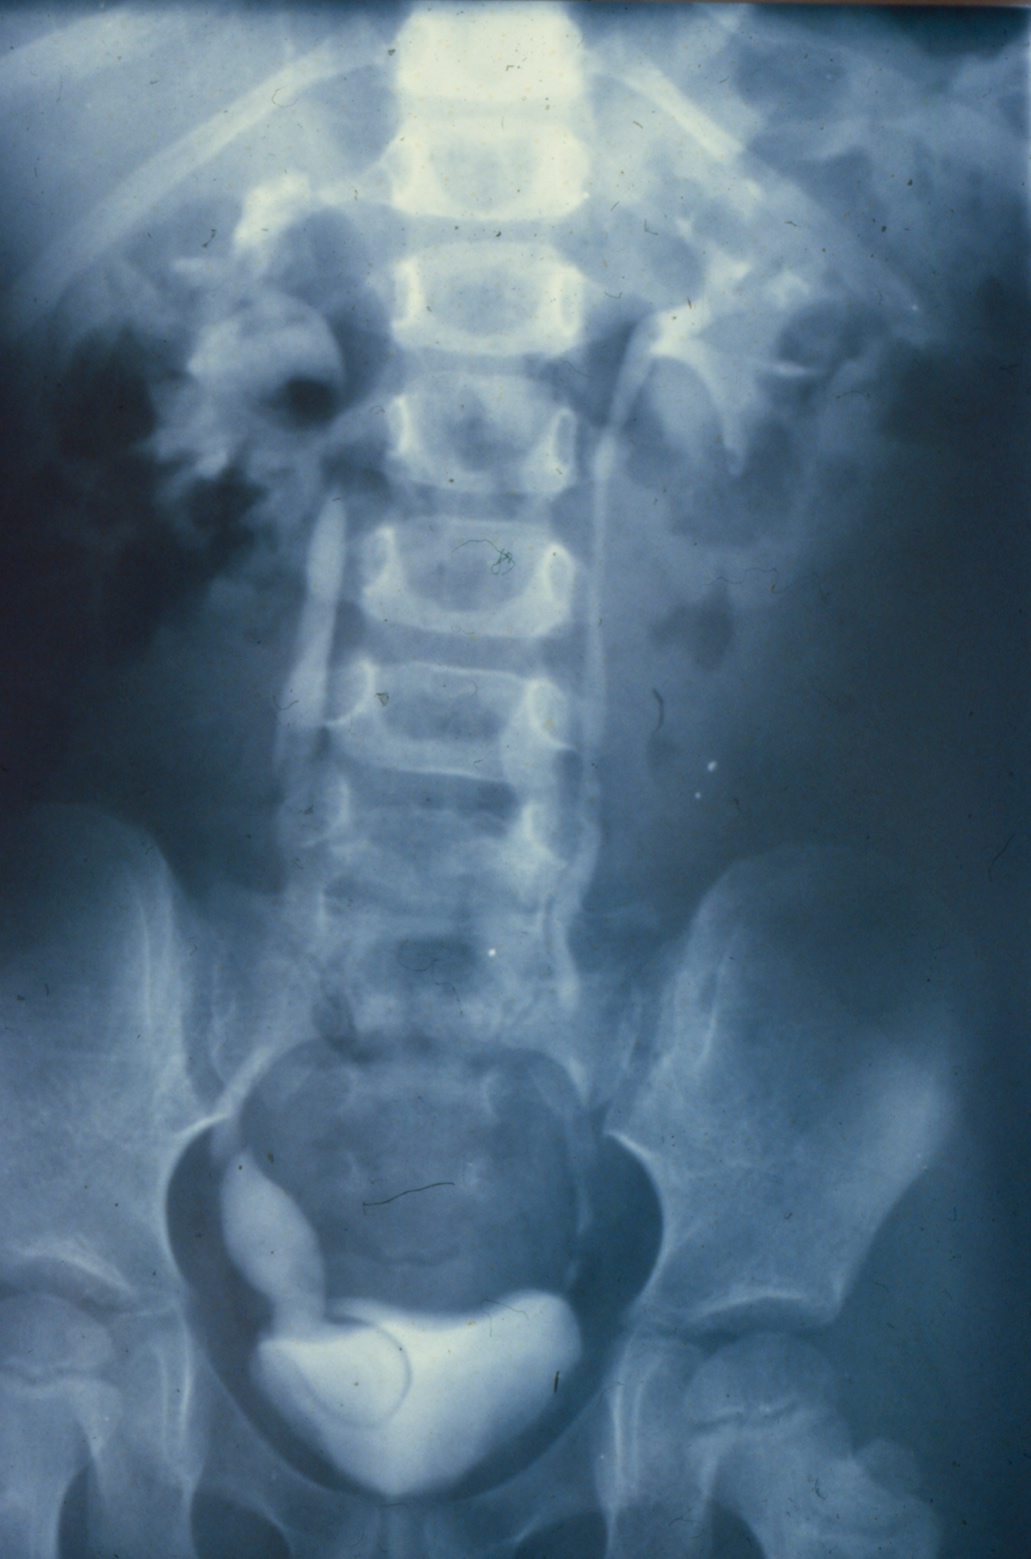

Introduction to Ureteroceles: Presentation, Diagnosis, and Initial Management

- Goals of ureterocele management include: prevention of renal damage, prevention of infection, and preservation of continence.

- Prenatal diagnosis of ureteroceles results in decreased morbidity both before and after surgical intervention.

- Patients presenting with obstruction and sepsis benefit from prompt, transurethral decompression.

- Any endoscopic technique chosen should aim to relieve obstruction while minimizing surgical morbidity and de novo reflux.